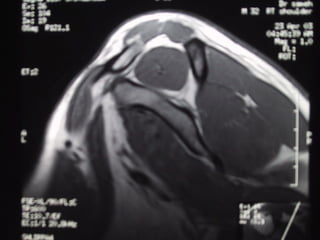

Case 5   Supraspinatus full thickness tear